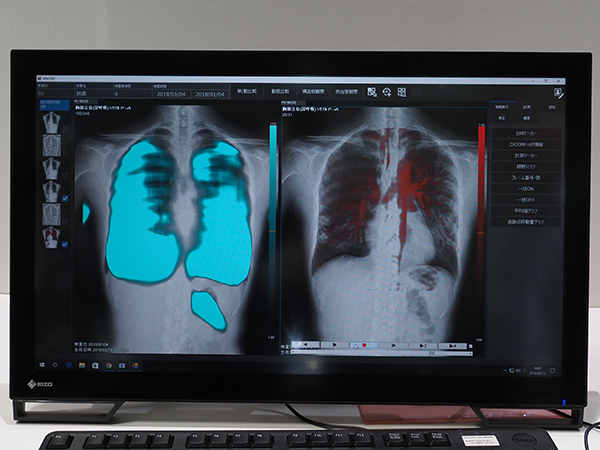

1933年に「さくらレントゲンフィルム」を発売して以降,コニカミノルタはX線撮影に関する製品・技術を世に送り出してきた。その連綿と続いてきた開発力の結晶が,2018年11月に発表されたX線動画解析ワークステーション「KINOSIS」である。“KINO”は“傑作な映画”と“機能”をかけており,“SIS”は,解析や診断を意味する。“技術をつなぐ”ことで世に送り出されたKINOSISは,一般X線撮影装置で撮影された画像を動画にして表示する。 島津製作所のX線撮影装置「RADspeed Pro」とコニカミノルタのワイヤレスFPD「AeroDR fine」,画像診断ワークステーション「CS-7」から得られたデータをKINOSISに送信して動画解析を行う。解析機能は,5モードを搭載している。視認性向上のための画像処理として,肺野内の肋骨や鎖骨の信号を減弱する“BS-MODE”,特定周波数を有する構造物の動きを強調する“FE-MODE”。構造物の動きを定量化する画像処理としては,肺尖部や横隔膜の動きを追跡する“DM-MODE”がある。また,動きに伴う信号値の変化を抽出する画像処理として,呼吸に伴う肺組織の動きによる信号値の変化をとらえる“PL-MODE”,血管の拍動による肺野内の濃度変化を可視化する“PH-MODE”がある。

X線動画解析ワークステーション「KINOSIS」